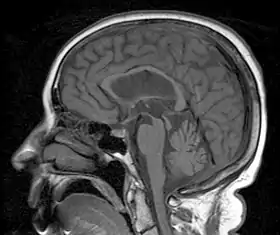

A person with progressive dementia, ataxia, and incontinence. A clinical diagnosis of normal-pressure hydrocephalus was entertained. Imaging did not support this, however, and on formal testing, abnormal nystagmus and eye movements were detected. A sagittal view of the CT/MRI scan shows atrophy of the midbrain, with preservation of the volume of the pons. This appearance has been called the "hummingbird sign" or "penguin sign". Also, atrophy of the tectum is seen, particularly the superior colliculi. These findings suggest the diagnosis of progressive supranuclear palsy.[1]

Magnetic resonance imaging (MRI) is often used to diagnose PSP. MRI may show atrophy in the midbrain with preservation of the pons giving a "hummingbird" sign.[27]